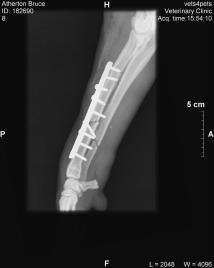

A midnight trip to the emergency vet room, followed by some work by an orthopaedic surgeon, resulted in a plate and 9 screws holding together his broken ulna and radius.

Broken ulna and radius.

Plated and screwed ulna and radius.

It also resulted in my being $4k poorer.